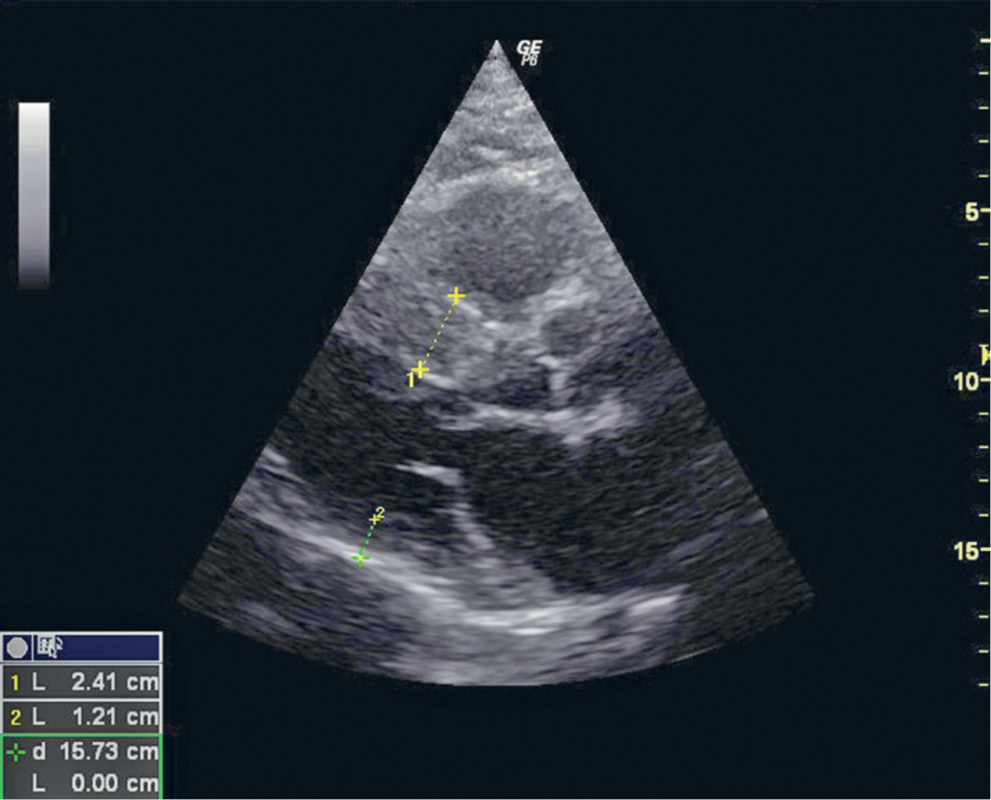

У отца (на момент обследования — 67 лет) ишемическая болезнь сердца манифестировала в возрасте 50 лет с развития стенокардии высокого функционального класса, в это же время были выявлены гипертрофия межжелудочковой перегородки, субаортальный стеноз. С 52 лет отмечались эпизоды потери сознания. В 2008 г. (60 лет) перенес инфаркт миокарда передней стенки ЛЖ, тогда же выполнялась коронароангиография; предлагалось оперативное лечение, от которого пациент отказался. Также у больного постоянная форма мерцательной аритмии, подагра, сахарный диабет 2-го типа. Анализ крови от 18.11.2015: общий холестерин 5,4 ммоль/л, холестерин ЛВП 0,97 ммоль/л, холестерин ЛНП 2,5 ммоль/л, триглицериды 4,14 ммоль/л (без липидснижающих препаратов). ЭхоКГ от 25.11.2015: межжелудочковая перегородка 2,4 см, задняя стенка левого желудочка 1,2 см, умеренная обструкция выносящего тракта ЛЖ (рис. 3). Нарушения локальной сократимости ЛЖ (гипокинез среднего сегмента межжелудочковой перегородки, гипоакинез верхушечного сегмента межжелудочковой перегородки), фракция выброса ЛЖ 56%, значительное расширение полостей предсердий.

Рис. 3. Эхокардиографическое исследование отца больного М.